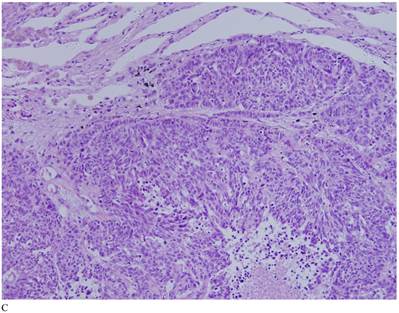

Case 1. A 79-year-old patient with a history of slowly increasing serum PSA levels for 2 years presented to the hospital with a 3-day history of fever. The patient's serum PSA level was 18.12ng/mL (normal <4ng/mL). Digital rectal examination (DRE) indicated grade III prostate enlargement. Magnetic resonance imaging (MRI) showed prostate cancer combined with right seminal vesicle invasion, pelvic lymph node, multi-bone, and liver metastases. An ultrasound-guided prostate biopsy was performed. Pathological examination suggested acinar adenocarcinoma. Gleason scores were 3+4=7. The patient was treated only with endocrine therapy because of his poor general condition. The patient died of respiratory failure caused by multiple metastases of the prostate cancer to both lungs 2 months later. Autopsy pathology revealed mixed SmCC of the prostate, combined with bilateral lung, liver, bilateral adrenal gland, pancreas, bone, and lymph node metastases. The prostate cancer was classified as SmCC with a mixture of acinar adenocarcinoma (Fig. 1A). All metastatic cancers were determined as pure SmCC without component of the acinar adenocarcinoma (Fig. 1B, 1C, 1D).

Case 1. Mixed SmCC. (A) Components of SmCC. (B) Components of acinar adenocarcinoma. Gleason scores were 3+3=6 combined with bilateral lung (C) and liver (D) metastases.

Two of our three cases of SmCC were mixed with acinar adenocarcinoma, and one was pure SmCC. Of the 26 cases in the literature reports, 21 cases were pure SmCC. Under the microscope SmCC tissues were flaky and in a nest-like distribution. Coagulative necrosis was also observed. The cells were small, like oat grains, with one end pointed and the other rounded. The cells contained only a small amount of cytoplasm, with the nuclei bared and darkly colored, and the nucleolus obscured; mitotic figures were frequently seen. For most cases, positive immunohistochemical staining for neurone-specific enolase (NSE), CD56, Syn, and CgA were detected, and immunohistochemical staining was positive for CK, producing a dot-like pattern. Local invasion, lymphatic vessel involvment, and distant metastases were found in 12 (46.2%), eight (30.8%), and nine cases (34.6%) respectively.

The confirmation of SmCC of the prostate relies mainly on pathological findings. Microscopically, SmCC cells are consistently round or short-spindle-shaped, arranged in a flaky or nest-like pattern. The cells only contain a small amount of cytoplasm, with the nuclei bared and darkly colored. The nucleolus is obscured and mitotic figures are frequently observed. Necrosis is also common. Immunohistochemical staining of SmCC cells for NSE, Syn, CgA, and CD56 is usually carried out for diagnosis [24]. Combined use of these four markers often results in a definitive diagnosis. Moreover, PSA, PAP, and P504S expression are rare in SmCC [8] and a CK-positive staining pattern in SmCC is characteristically dot-like. This can be used to differentiate SmCC from the poorly differentiated acinar adenocarcinoma.